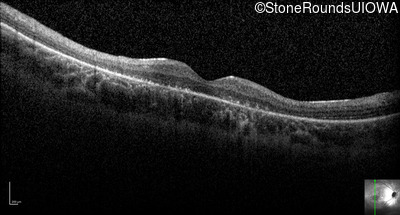

Optical Coherence Tomography - Right - 10/120 +1

Exemplar / OCT Stack